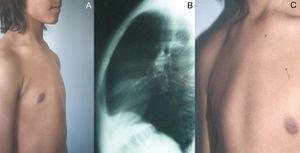

Se trata de un varón de 13 años de edad, sin antecedentes medicoquirúrgicos de importancia, con pectus carinatum asimétrico de aparición aproximadamente a los 7 años de edad, que aumentó de volumen hasta la actualidad (figs. 1A y C). El joven pesaba 55 kg y medía 1,65 m de estatura. Su capacidad funcional pulmonar y su función cardíaca eran normales. Manifestaba un firme deseo de corregir su malformación dados los conflictos que le ocasionaba en su vida de relación. La radiografía torácica de perfil mostraba la incurvación esternal hacia delante (fig. 1B). La región anterior del tórax era compresible, en tanto que se verificaba una expansión bilateral en los cartílagos y arcos costales de la región axilar inferior.

Fig. 1. Paciente varón de 13 años de edad. Imágenes preoperatorias: oblicua derecha (A), radiografía preoperatoria (B) y oblicua izquierda (C).